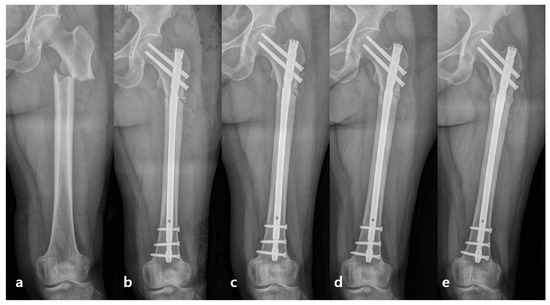

Decortication in the Surgical Management of Complete Atypical Femoral Fractures: A Strategy to Accelerate Fracture Healing

by Young-Ho Cho, Changhun Lim and Dongha Kim

J. Clin. Med. 2026, 15(2), 436; https://doi.org/10.3390/jcm15020436 - 6 Jan 2026

Abstract

Background/Objectives: Surgical management of atypical femoral fractures (AFFs) stabilized with intramedullary (IM) nailing is frequently challenged by delayed union or nonunion due to the severely suppressed bone turnover characteristic of bisphosphonate-related bone pathology, often leading to a hypertrophic nonunion-like state at the fracture [...] Read more.

Background/Objectives: Surgical management of atypical femoral fractures (AFFs) stabilized with intramedullary (IM) nailing is frequently challenged by delayed union or nonunion due to the severely suppressed bone turnover characteristic of bisphosphonate-related bone pathology, often leading to a hypertrophic nonunion-like state at the fracture site. This consecutive case series aimed to evaluate the effectiveness of intraoperative percutaneous decortication at the hypertrophic cortex in promoting rapid bone healing in complete AFFs. Methods: This was a single-center consecutive case series of patients with complete atypical femoral fractures (AFFs) treated with intramedullary nailing and adjunctive percutaneous decortication since February 2021. The standardized surgical protocol—including percutaneous decortication performed through a small anterolateral incision using an osteotome to create bone chips and stimulate the sclerotic cortex—was applied prospectively to all consecutive patients from February 2021. Of the 20 patients who underwent surgery during this period, 14 with sufficient radiographic follow-up were included in the final retrospective analysis. Data collected included patient demographics, duration of bisphosphonate use, fracture location (diaphyseal vs. subtrochanteric), operative details (including iatrogenic fracture), and radiographic bone union time. Bone union was assessed on serial radiographs by two independent observers. Results: All 14 patients were female, with a median age of 75 years (IQR 67–79 years). Thirteen patients (92.9%) had prior bisphosphonate exposure for a median of 4.5 years (IQR 3–10 years). Six fractures were subtrochanteric fractures, and six were complicated by iatrogenic fracture during nail insertion. Postoperative teriparatide was administered to six patients. Radiographic bone union was achieved in all 14 patients at a median of 19 weeks (IQR 16–22 weeks; range 16–24 weeks). No major complications (infection, implant failure, nonunion, or neurovascular injury) occurred during follow-up. Conclusions: Percutaneous decortication is a simple, safe, and biologically plausible adjunct to intramedullary nailing. In this series of 14 elderly women with long-term bisphosphonate exposure (median 4.5 years), the technique was associated with 100% radiographic union at a median of 19 weeks without major complications, suggesting a promising strategy that warrants validation in larger, controlled trials. Full article

(This article belongs to the Special Issue Accelerating Fracture Healing: Clinical Diagnosis and Treatment)

Show Figures